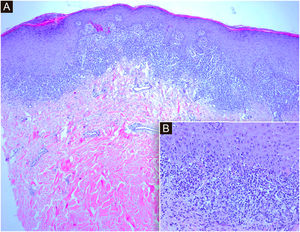

A histopatologia mostrou hiperceratose, corpos citoides e infiltrado inflamatório subepidérmico em faixa composto por linfócitos, histiócitos e eosinófilos ocasionais na derme papilar (fig. 3). As características favoreceram o diagnóstico de LP.3 As sorologias para vírus da hepatite B (VHB) e C (VHC) foram negativas. Foi prescrita pomada de propionato de clobetasol a 0,05% por quatro semanas com resposta parcial.

(A) Cortes histológicos mostram epiderme com hiperceratose ortoceratótica e paraceratose focal, acantose com hipergranulose e denso infiltrado inflamatório subepidérmico em faixa consistente com dermatite de interface (Hematoxilina & eosina, 4×). (B) No detalhe observa‐se dermatite de interface linfocítica com degeneração vacuolar da camada basal e queratinócitos necróticos na epiderme (Hematoxilina & eosina, 20×)